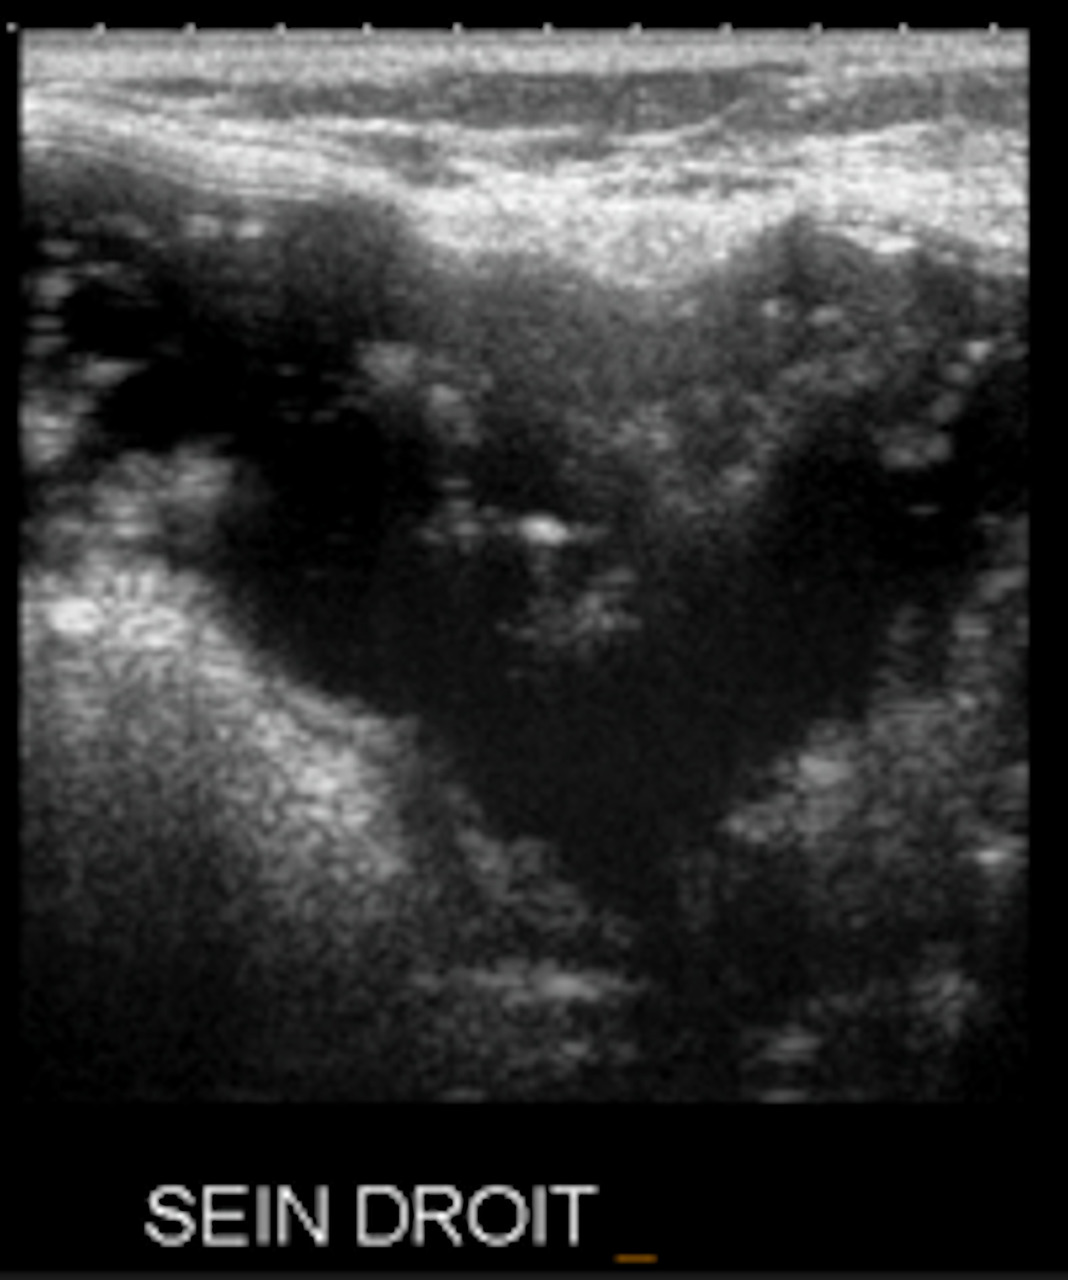

• extracapsulaire (fig. 3 et 4), contenu hétérogène avec échos internes et perte du contour régulier de la paroi à l’échographie. Diagnostic confirmé par l’IRM mammaire avec séquences dédiées silicone, qui montre l’incontinence de la prothèse (paroi irrégulière) et des dépôts de silicone rétro- ou périprothétiques. Des ganglions chargés en silicone peuvent être visibles.